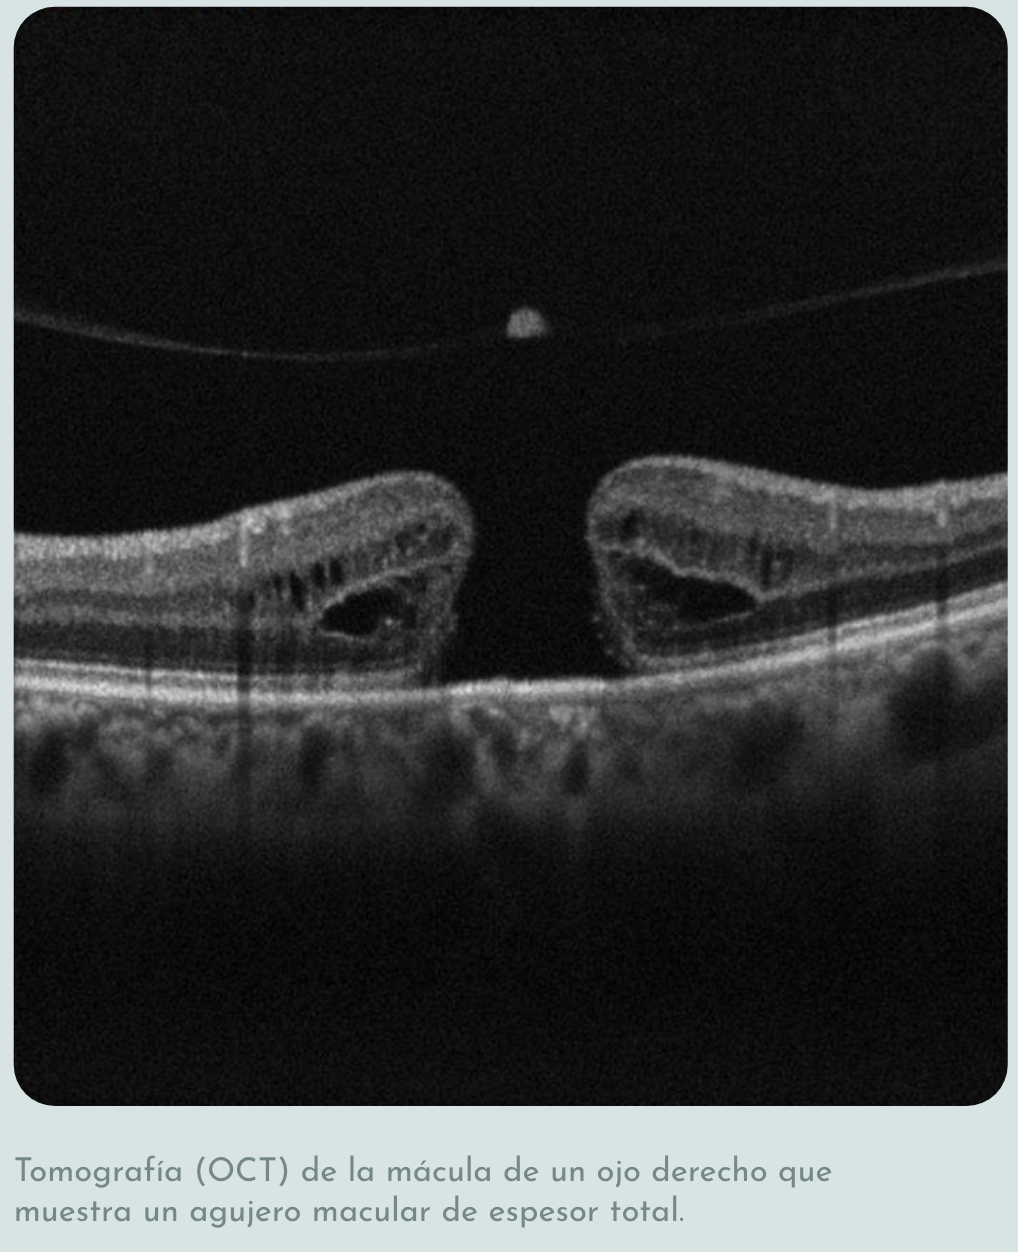

El diagnóstico se realiza mediante una exploración oftalmológica. La tomografía de coherencia óptica (OCT) de la mácula es fundamental para confirmar el diagnóstico, determinar el tamaño del agujero y clasificar su etapa, lo cual es clave para decidir el tratamiento.